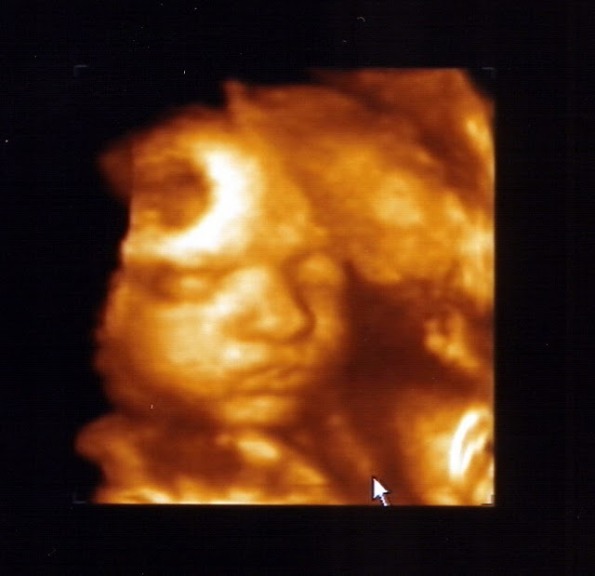

Babi, sztem totál apukája. ( bár nagyon vágyom rá, hogy belőlem is jusson)

( a képen jól látszik, hogy a köldökzsinórt, mint 1 sálat, úgy használja, végülis téli -gyerek.

)